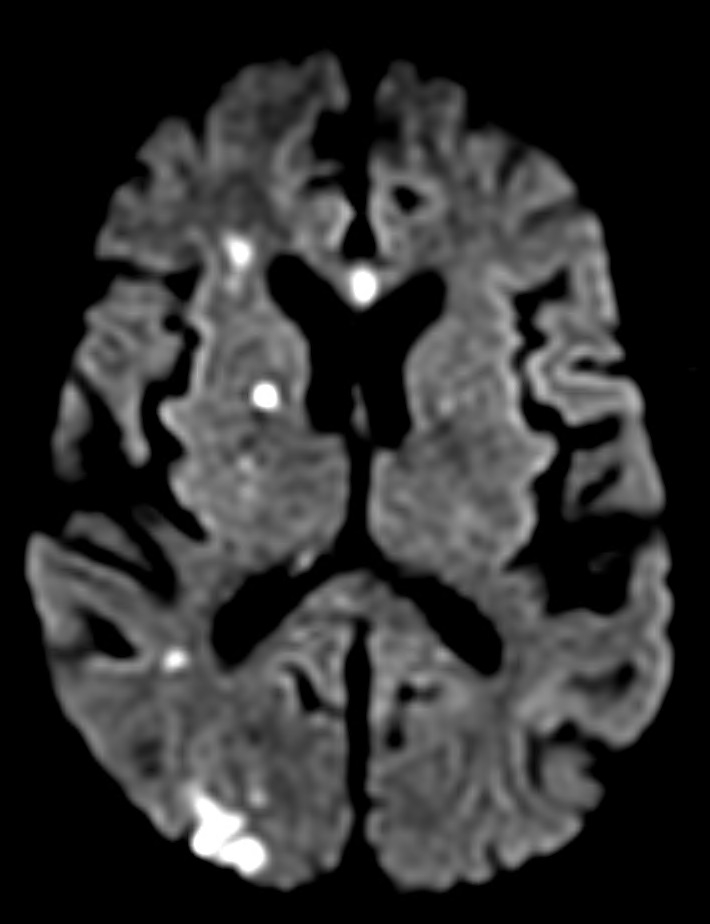

Methods: We performed a retrospective analysis of brain MRI reports from patients with cardiac arrest in a multicenter cohort to evaluate the incidence of acute ischemic stroke and HIBI. Patients with MRI in the first 7 days after cardiac arrest were included. Patients with traumatic brain injury, intracranial hemorrhage, recent neurosurgical procedures, or ischemic stroke at admission were excluded. A secondary manual review by a board-certified vascular neurologist was pursued if the MRI report did not specify the absence of ischemic stroke. Univariate and multivariable analysis was performed to explore the characteristics of the ischemic lesions and to evaluate if it was related to poor functional outcomes (i.e., Cerebral Performance Category of 4-5).

Results: Among 396 patients who met the inclusion criteria, 91 had cerebral infarction based on MRI (22.9%). The most common pattern of stroke was multifocal small embolic (51.6%), followed by single embolic (25.3%), watershed (12.1%), territorial (7%), and lacunar (5%). The patients with acute ischemic stroke were older (p<0.01). In the logistic regression, older age, non-witnessed cardiac arrest, and non-shockable rhythm were associated with worse prognosis (p<0.05). The presence of acute ischemic stroke was not significantly associated with the cause of arrest, percutaneous coronary intervention (PCI), or the use of targeted temperature management (TTM). Individuals with acute ischemic stroke had lower rates of HIBI (odds ratio [OR] 0,55 [0.34-0.87], p<0.01). In univariate and multivariate analysis, the presence of acute ischemic stroke was not associated with outcome, as opposed to the presence of HIBI (p<0.01).

Conclusion: More than one-fifth of the comatose patients after cardiac arrest present acute ischemic stroke on MRI. The most common pattern is multifocal embolic, which may be related to cardiac embolism and hypercoagulable state after the arrest and not from PCI or cardiac arrest rhythm. The detection of acute ischemic stroke is higher among individuals without HIBI and is not associated with worse outcomes.